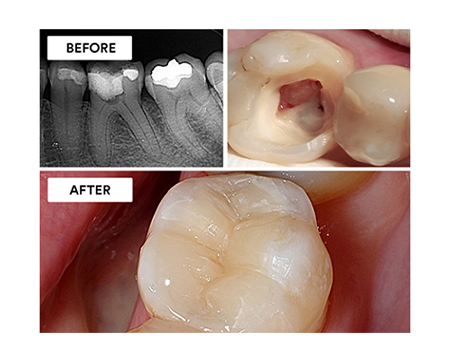

Clinical Case: Preserve & protect: Adhesive endocrown restoration

Using 3M™ Scotchbond™ Universal Plus Adhesive and 3M™ RelyX™ Universal Resin Cement.

Clinical Case: Root canal treatment and post-endodontic restoration

Using 3M™ Scotchbond™ Universal Plus Adhesive, 3M™ Filtek™ Supreme Flowable Restorative, 3M™ Filtek™ One Bulk Fill Restorative and 3M™ Filtek™ Universal Restorative.